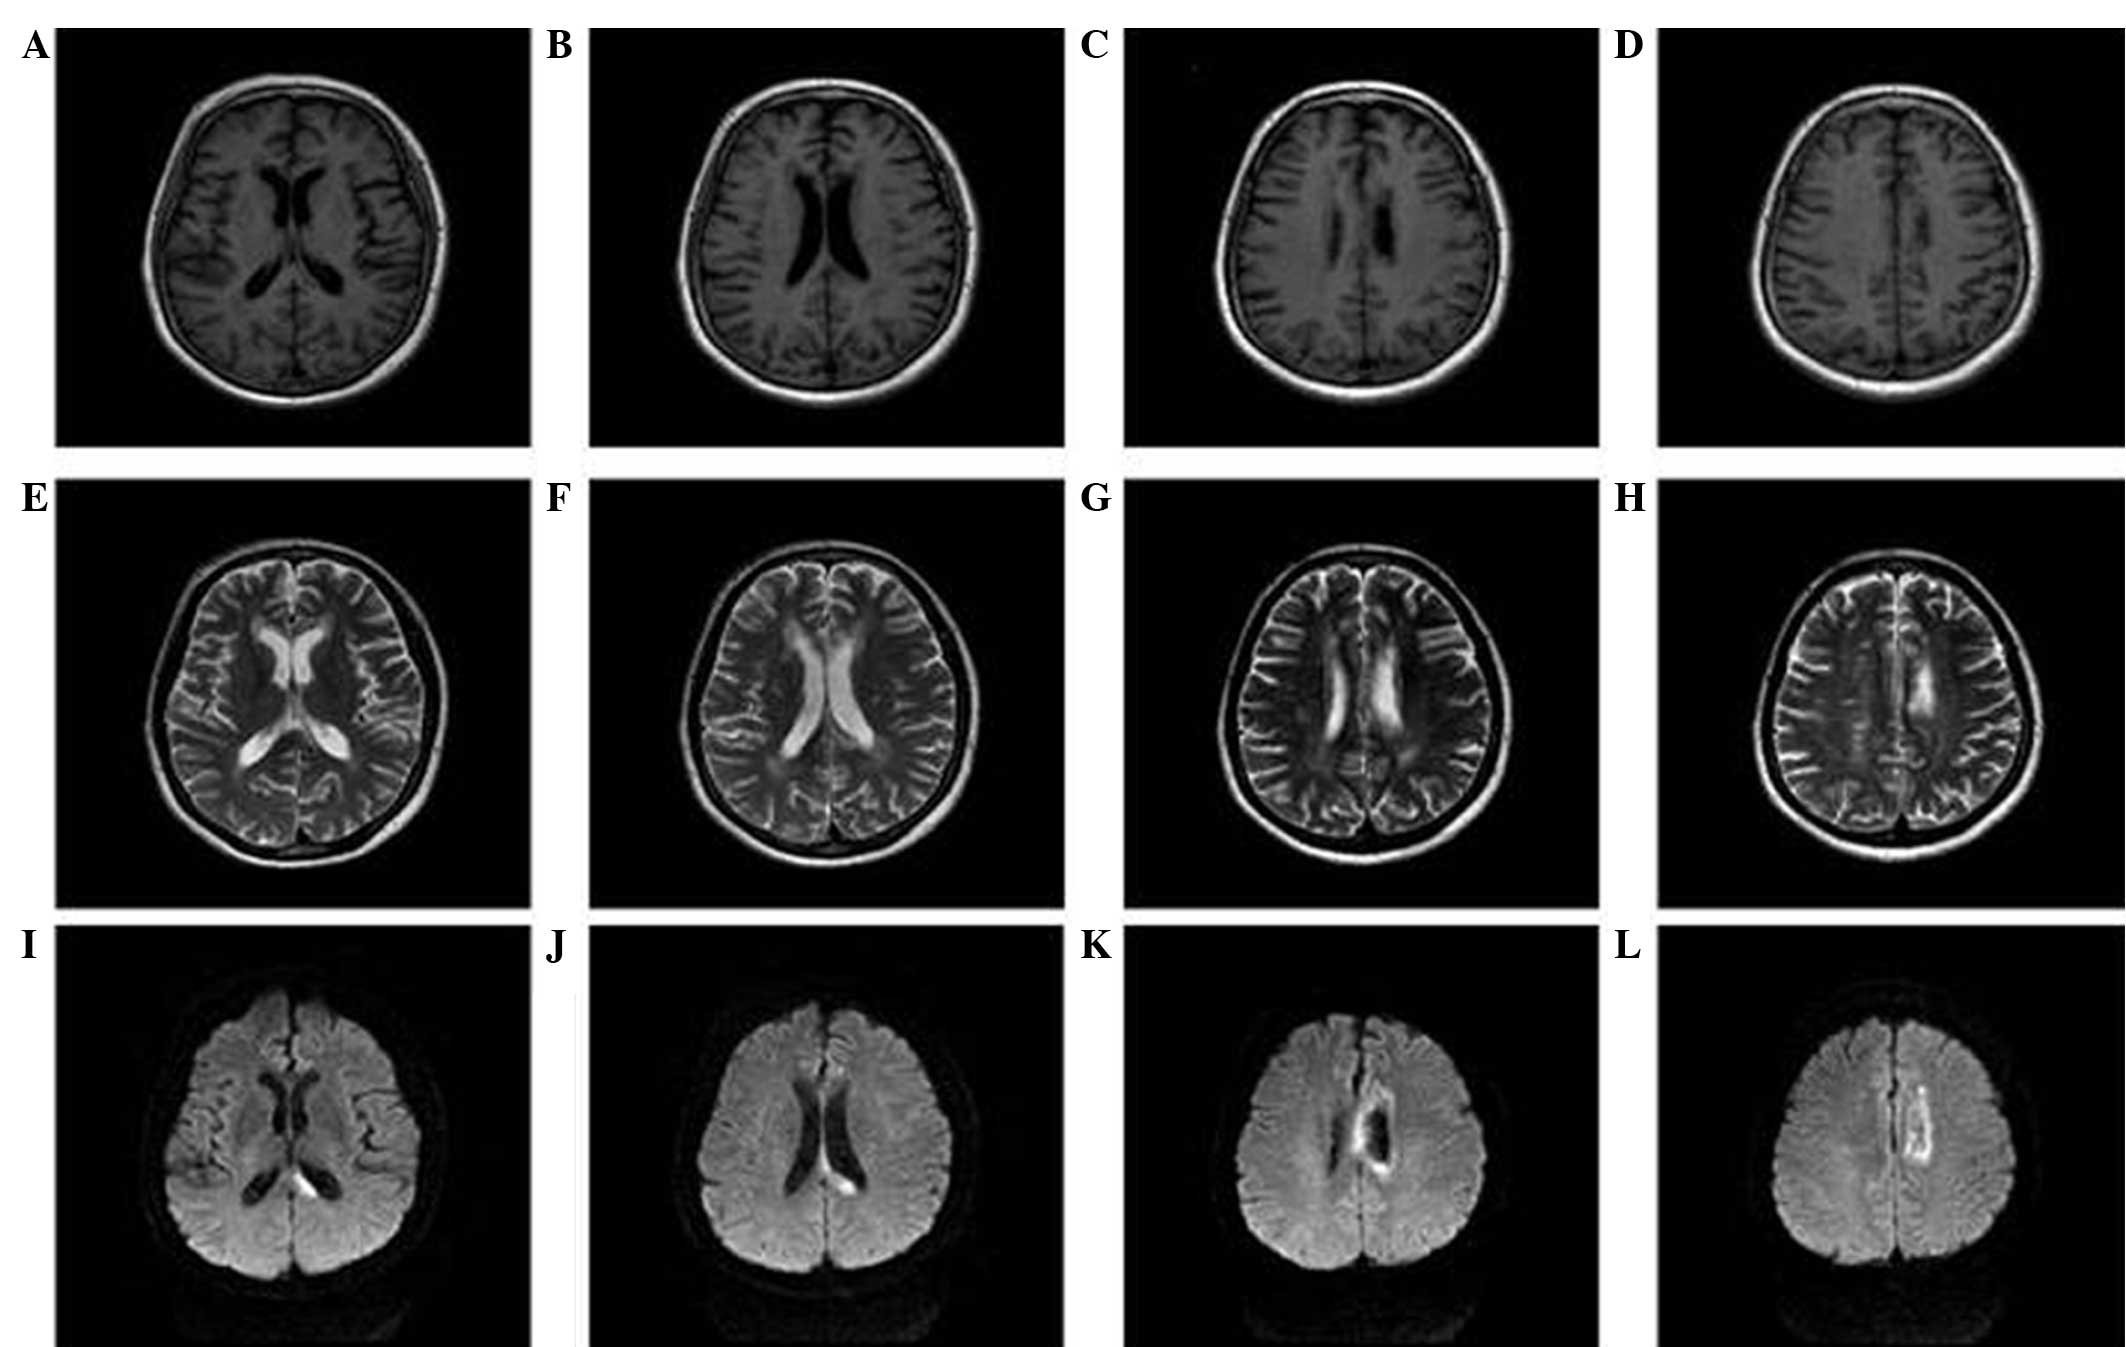

Pdf Pathophysiology And Treatment Of Alien Hand Syndrome

Involuntary Hand Levitation Associated With Parietal Damage Another Alien Hand Syndrome